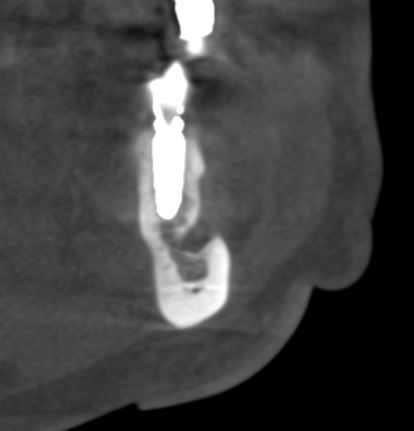

Но, насколько долговечен подобный результат остеопластики? Посмотрим на КЛКТ через 18 месяцев:

или

Как видите, даже структурно регенерат не отличается от подлежащего альвеолярного гребня, хотя заметен на снимке своей неестественной формой. Это говорит о том, что результат остеопластической операции стабилен, и мы можем быть спокойны за дальнейшую судьбу имплантов.